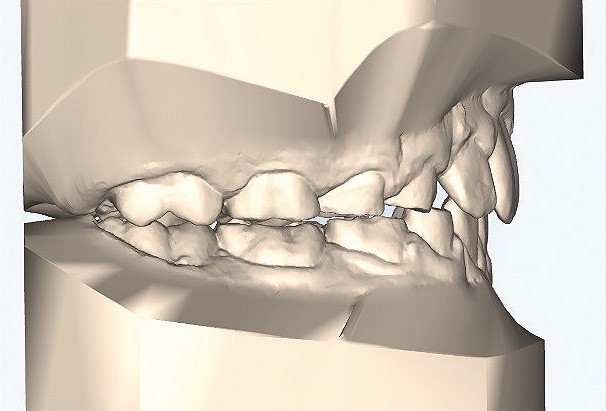

Klinisches Fallbeispiel 2 (Abb. 2a–y)

Distalbiss und tiefer Biss bei einem zwölfjährigen Mädchen. Die Behandlung erfolgte mit Invisalign und Precision Wings. Insgesamt waren zwei Schienensätze notwendig. Die Gesamtbehandlung dauerte 18 Monate.Bei der Planung des ClinCheck wurde der tiefe Biss vorwiegend über eine Intrusion der Unterkieferfront behoben, um die Lachlinie der Patientin nicht negativ zu beeinflussen. Die Oberkieferfront wurde nur retrudiert, jedoch vertikal nicht intrudiert. Während der Phase des Mandibular Advancement wurde die Wirkung der Precision Wings durch den Einsatz von Klasse II-Gummizügen unterstützt. Schlussendlich wurde auch der hängenden Okklusionsebene durch eine einseitige Intrusion der Molaren im ersten Quadranten Rechnung getragen.